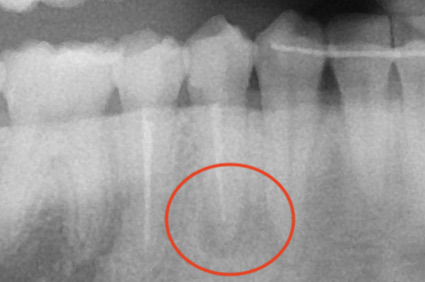

レントゲン

右下4番の根尖部に黒い透過像がありますね。(赤丸で囲ったところ)

やはりありました。もう一つの根管。

1根じゃなく2根管だったのね。

これで透過像の謎が解けました。

赤丸が2根管目。

こちらは根充後のレントゲン。

心なしか初診時の写真の時より、透過像が小さくなっているような気がします。